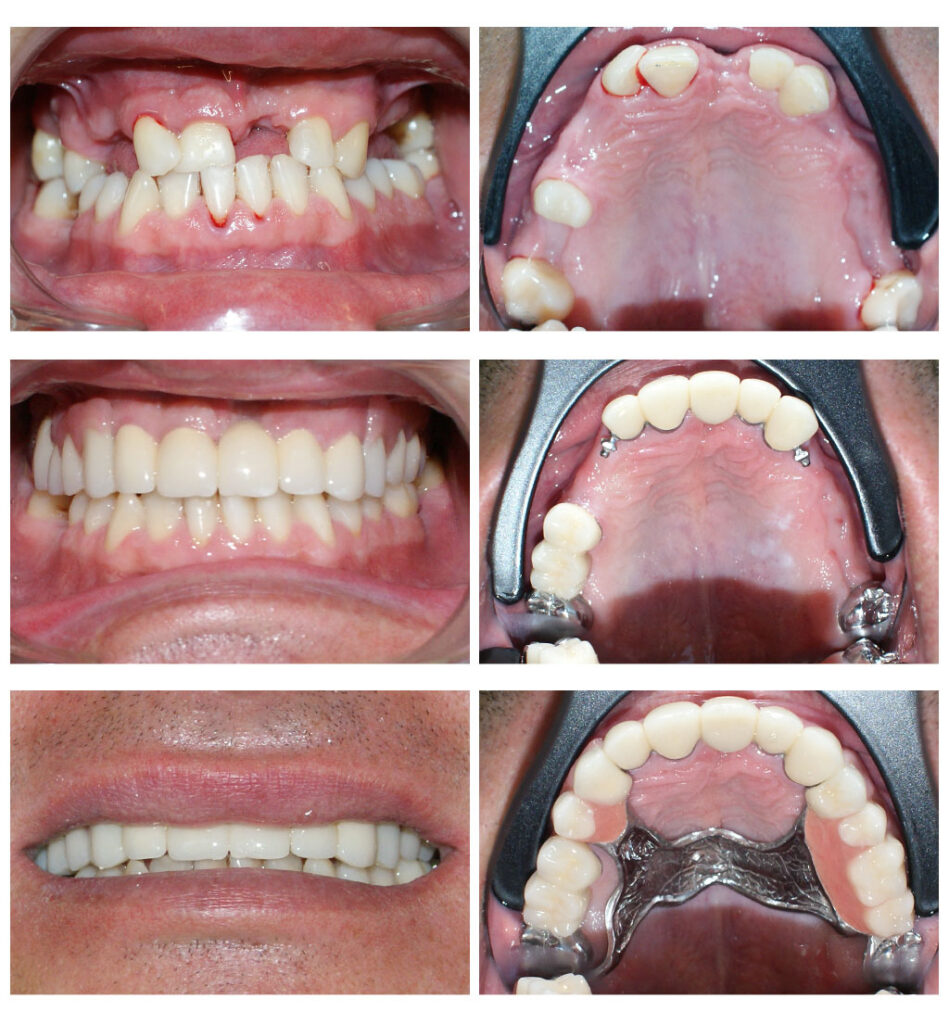

Proteza telescopată – stabilitate perfectă

Proteza telescopată  și proteză scheletată aplicate pe dinții tratați corect! Execuția riguroasă oferă stabilitate excelentă.

Lucrare fixată pe dinți împreună cu proteză scheletată mobilizabilă = soluția de lux pentru dinți puțini